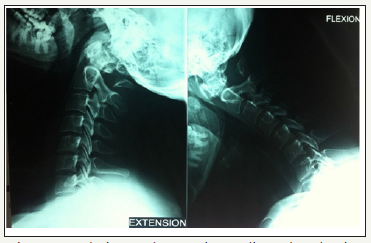

Simple radiography (Rx) revealed the existence of a partial defect in the posterior arch of C1 with a preserved posterior tubercle (Currarino type D) (Figure 1). We verified the stability of the tubercle through radiography in flexion and extension (Figure 2). Computed tomography (CT) images with three-dimensional (3D) reconstruction demonstrated the absence of the posterior arch and the presence of a persistent posterior tubercle (Figure 3). No evidence of compression of the spinal cord was shown on magnetic resonance imaging (Figure 4). The patient benefited from a symptomatic treatment with anti-inflammatory and analgesic drugs. Her symptoms decreased within 48 hours. She was asked to avoid contact sports, athletic activities and any activity or situation which could cause the cervical hyperextension.

Figure 2: Flexion and extension radiographs showing absence of the posterior arch of the atlas without evidence of atlatoaxial instability.